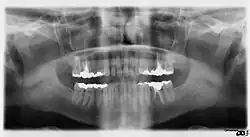

Панорамная рентгенограмма показывает нижние зубы мудрости с горизонтальным ретинированием